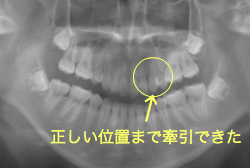

牽引(埋伏犬歯を牽引した症例)

埋伏歯とは、骨または歯茎の下に埋まって出てこない状態の歯のことを言います。埋伏歯があると歯が押されて歯並びが悪くなってしまったり、永久歯が生えてこれない原因になる恐れがあります。

「乳歯が生え替わらない」という主訴で来院したケースです。 診断の結果、「左上永久犬歯が第一小臼歯後方上部に埋伏しているため、左上乳犬歯が晩期残存している症例」と判明しました。

このような症状の場合は、手術で埋伏している永久歯に金具を取り付け、矯正装置で牽引する必要があります。同時に凸凹の解消と前突した前歯を内側に入れるために上下左右の小臼歯を抜歯させて頂くことといたしました。

この方の場合は、マルチブラケット装置にて治療を開始し、治療期間2年3ヶ月で終了しました。犬歯の牽引距離が非常に大きかったため当院の平均治療期間よりも大幅に期間がかかりましたが、埋伏犬歯を完全に正しい位置まで誘導することができました。同時に 前歯の前突と配列の凸凹も解消しました。

このような症例は、成人してしまうと埋伏歯の反応性が悪く、あまりにも動きが悪い場合は牽引をあきらめて抜歯する場合もあります。歯科医院の検診で親知らず以外の埋伏歯を指摘された場合は、できるだけ早く矯正専門医に御相談下さい。